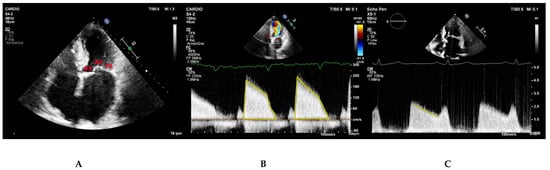

5.2. Parasternal Short-Axis View

5.3. Apical Four Chamber View

5.4. Classification of Mitral Stenosis Severity